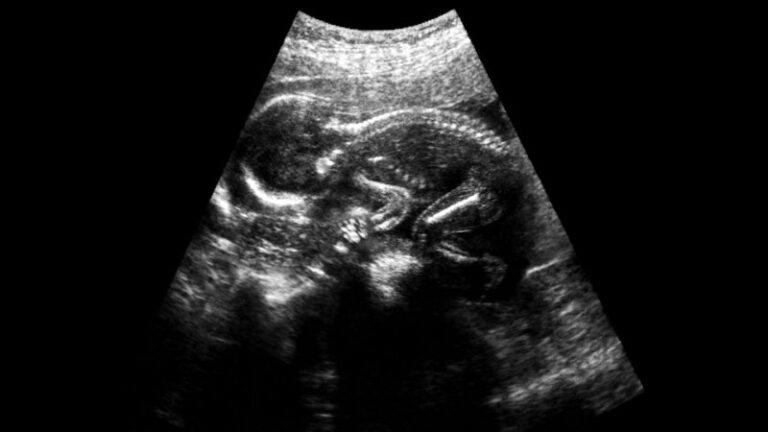

sciencenews This dangerous pregnancy complication is common. A new treatment might help mforghan April 27, 2026 Preeclampsia complicates 3 to 8 percent of pregnancies. In a recent trial, a blood filter lowered blood pressure and helped prolong some pregnancies. Post navigation Previous: نابرابری در توزیع ثروت زیر ذرهبین افکار عمومی آلمانNext: Physicists Discover the Most Complex Forms of Ice Yet